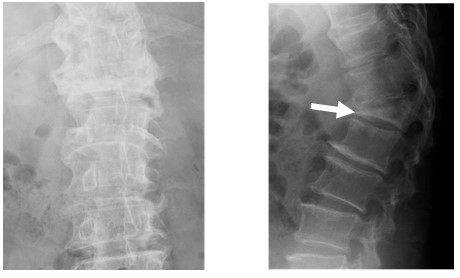

破裂骨折は圧迫骨折に比べて格段に治療が難しくなります。圧迫骨折と診断されたら、早めに医療機関を受診し、適切な治療を受けてください。 3.圧迫骨折の臨床症状 (1)急性期症状 ある時突然、背中や腰に強い痛みが起こります。従来より、「脊椎圧迫骨折」の治療方法には以下のような方法があります。 <治療法1> 脊椎圧迫骨折の「保存的療法」 コルセットやギプスを装着したり、ベッドの上で安静にしたりします。脊椎圧迫骨折の基礎知識 point 脊椎圧迫骨折とは 背骨は骨がいくつも重なり合っています。その中の背骨の1つが圧迫されて押しつぶされてしまうことを脊椎圧迫骨折と言います。高齢の女性に多く見られ、「寝たきり」の原因になります。

骨粗しょう症による脊椎圧迫骨折の基礎と診断 せぼねと健康 Com